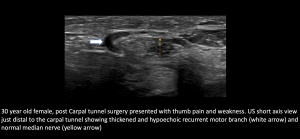

- Post Carpal Tunnel Release (CTR) surgery, Palmar Cutaneous Branch (PCB) neuroma and Flexor Carpi Radialis (FCR) tenosynovitis

Fig 14: POST CTR SURGERY PALMAR CUTANEOUS BRANCH (PCB) NEUROMA AND FCR TENOSYNOVITIS PCB neuroma and PCB hydrodissection with steroid injection

Fig 15: POST CTR SURGERY PALMAR CUTANEOUS BRANCH (PCB) NEUROMA AND FCR TENOSYNOVITIS Normal Median Nerve at Carpal tunnel; Persistent PCB neuroma